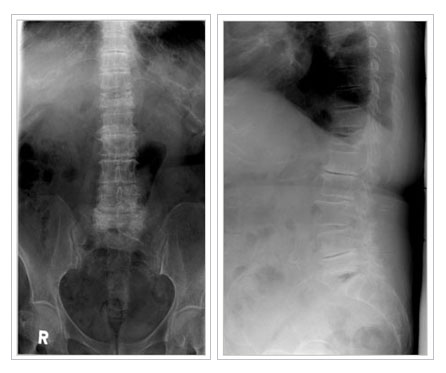

°ñ´Ù°øÁõ¼º ôÃß

°ñ´Ù°øÁõÀº ¾à¹°Ä¡·á, ¿îµ¿ ¹× ½ÄÀÌ¿ä¹ýµîÀÇ º¸Á¸Àû Ä¡·á·Î ´ëºÎºÐ Àß ÇØ°áµÉ ¼ö ÀÖ½À´Ï´Ù. °ñÀýÀÌ »ý±ä °æ¿ì´Â ¾ÈÁ¤°ú º¸Á¶±â µîÀ¸·Î Ä¡·áÇÏÁö¸¸ ¼ö¼úÀû Ä¡·á°¡ ÇÊ¿äÇϱ⵵ ÇÕ´Ï´Ù. ôÃß°ñÀýÀÇ °æ¿ì¿¡´Â ÇǺÎÀý°³¸¦ ÇÏÁö¾Ê´Â ÃÖ¼Ò Ä§½ÀÀû ½Ã¼úÀÌ ÀÌ¿ëµË´Ï´Ù. ±×·¯¹Ç·Î Á¶±â¿¡ Ä¡·á ¹× ¿¹¹æÀ» öÀúÈ÷ ÇÏ´Â °ÍÀÌ Áß¿äÇÕ´Ï´Ù.